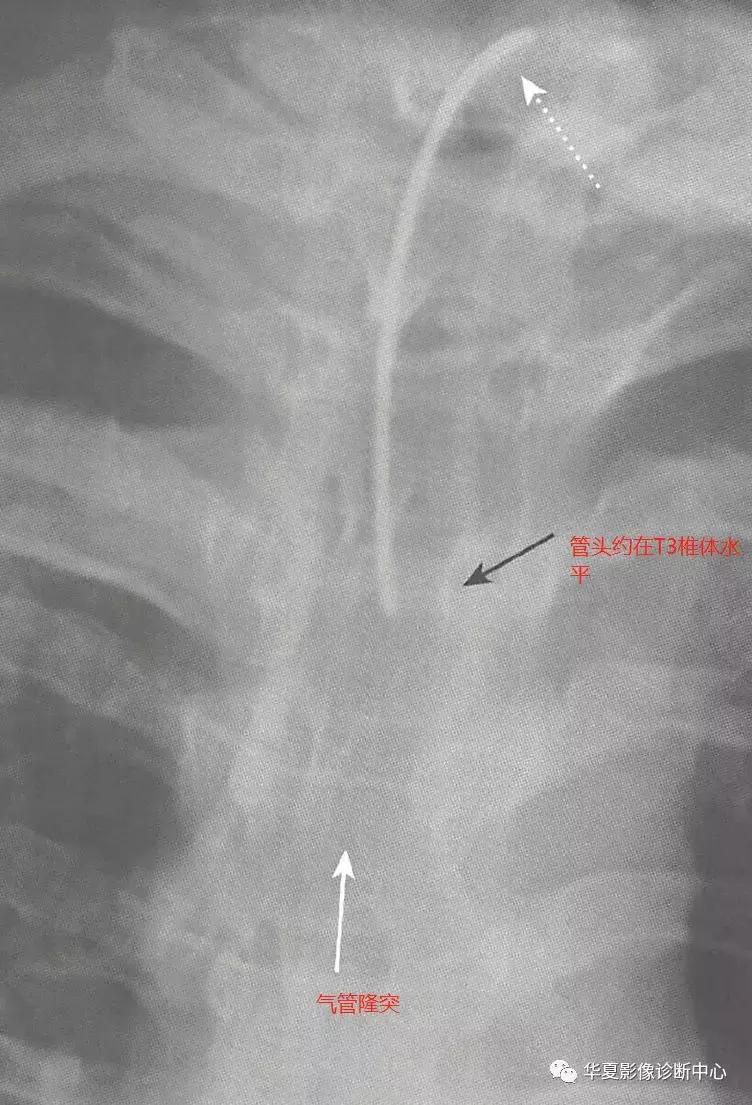

二、气管切开插管

管头应位于气管切开处和隆突之间的中间位置,相当于T3椎体水平,与ETT不同,气管切开插管管头的位置不受颈部前屈和后仰的影响,气管切开插管管径应约为气管宽度的2/3,若有气囊,通常充气后不应大于气管腔,短期并发症为可能发生气管穿孔(纵隔气肿、气胸、皮下气肿等),气管狭窄是最常见的长期并发症,常发生在切口处。